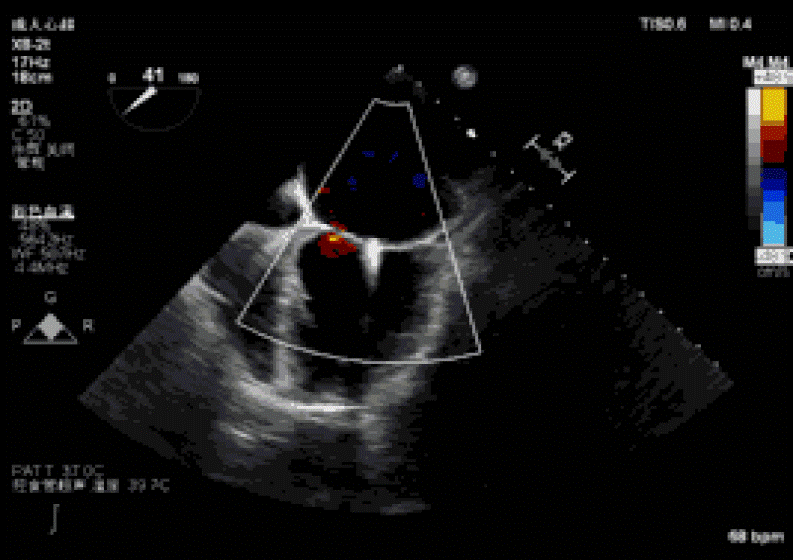

2019年3月5日中午,复旦大学附属中山医院葛均波院士团队的周达新教授、潘文志副主任医师,心外科的魏来教授、杨晔主治医师,心超室的潘翠珍教授、李伟主治医师,麻醉科的郭克芳教授,使用最新一代心脏超声机器Philips EPIQ 7C,完成一例经心尖二尖瓣夹合术。新一代超声机器分辨率高,图像处理速度快,图像界面舒适,使得手术非常顺利。导管操作时间(从穿刺心尖到闭合心尖时间)仅10分钟。患者术后即刻效果满意,反流从重度减少到轻微。本例是国内首例使用最新一代心超机器Philips EPIQ 7C的X8-2t食道探头进行术中经食道超声,采用TrueVue心腔镜成像技术指导心脏介入手术,获得满意的结果。